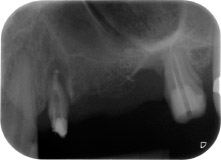

Une patiente de 58 ans se plaignait de douleurs et d'une mobilité accrue de la dent pilier 24 de son bridge. Présence d'une inflammation parodontale avec formation de poches de 7 mm de profondeur dans le sens mésiobuccal et de plus de 12 mm dans le sens distal, ainsi que d'une atteinte de la furcation au troisième degré. La radiographie a par ailleurs révélé une lésion parodontale étendue autour de la région apicale de la dent 24 ayant préalablement reçu un traitement endodontique (alio loco) (Fig. 1).

Un an plus tôt, les dents 25 et 26 avaient été extraites à la suite d'un traumatisme et pour cause d'atteinte endo-parodontale, avant la pose du bridge. Une lésion endo-parodontale combinée a été diagnostiquée pour la dent 24, d'étiologie incertaine. La patiente voulait conserver ses dents piliers 24 et 27 et refusait toute prothèse amovible à titre définitif, et même provisoire. Par conséquent, malgré un pronostic défavorable compte tenu des résultats des radios et des examens cliniques, il a été convenu de faire le maximum pour conserver les deux dents.

À la racine de la dent, il manquait la totalité de l'os vestibulaire et distal. L'attache était essentiellement limitée à la racine palatine, venant ainsi confirmer le pronostic défavorable initial. La dent 27 présentait également une attache horizontale réduite et une raréfaction apicale minime (cf. Fig. 1), sans symptômes cliniques.